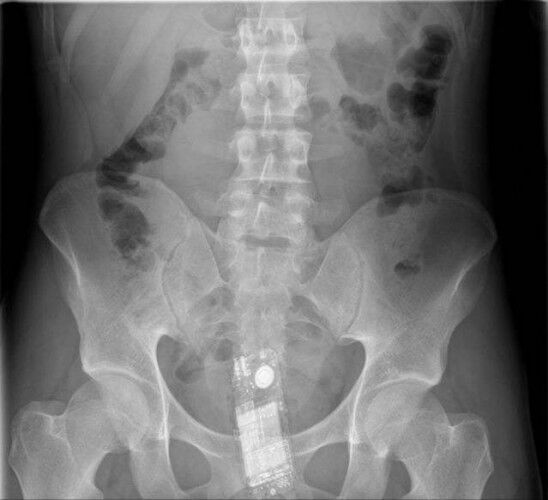

Röntgen Filminde İnsanların İçinden Çıkan Acayip Maddeler

2 / 9